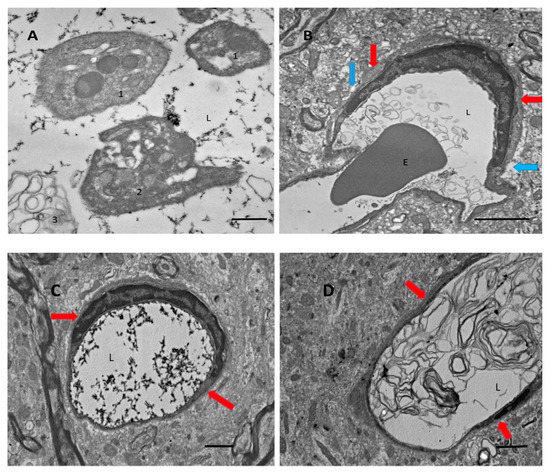

Previously, we found that there is a massive release of Aβ during thrombosis [8]. In this study, we used electron microscopy to analyze blood vessels within the affected areas of the brain after ischemic stroke, and we looked for characteristic signs of coagulation. We found that vessels, especially small vessels, are filled with clot-related elements, such as fibrin strands (Figure 1A,C), clot-related debris (Figure 1B,D), and different forms of platelets (Figure 1A). Platelets also showed clot-related morphological conversions, from a relatively rounded form (Figure 1A, “1”), to stellate (Figure 1A, “2”), and then to a fully degranulated form (Figure 1A, “3”). Fibrin strands fill the majority (≈60%) of blood vessels in the ischemic zone (Figure 1C, also at high magnification in Figure 1A). Many vessels are also filled with debris that looks like lipid membrane bubbles (Figure 1B,D). Astrocyte endfeet, which envelop blood vessels walls in many cases, appear swollen (Figure 1, blue arrows), whereas basal membranes in perivascular spaces are expanded in volume (Figure 1, red arrows).

Figure 1. Blood vessels after transient middle cerebral artery occlusion (tMCAO) under the electron microscope. (A) Platelets, rounded and stellate (see text). (B) Erythrocyte (E) entrapped in debris. (C) Fibrin strands in the vessel lumen (L). (D) Significant swelling and vacuolar bubbles in the astrocyte endfeet around the blood vessels (blue arrows). Perivascular space (red arrows). Scale bars: (A), 500 nm; (B), 2 µm; (C,D), 600 nm.

The present work established the presence of Aβ peptide in the ipsilateral part of the brain after tMCAO. Using electron microscopy, we also confirmed that in the damaged brain regions following tMCAO, the majority of small blood vessels showed signs of coagulated blood within and showed a clear swelling of astrocyte endfeet surrounding the blood vessels. This coagulation could be a source of Aβ, as was proposed elsewhere (see review in [2]). Blood coagulation produces massive amounts of Aβ peptides from the amyloid precursor protein (APP) liberated from platelets during experimental photothrombosis of brain blood vessels [8] and during experimental thrombosis of blood vessels in the skin [9] (Figure 1A–D). Aβ peptides are abundantly accumulated on the walls of small blood vessels, most likely on the external walls (Figure 2A,B), in some capillaries, and probably in astrocyte endfeet (Figure 2A). Our experiments showed that Aβ is present mainly in its non-aggregated form, which is recognized by a specific anti-Aβ-antibody, whereas only a small amount of aggregated Aβ, which is stained with Congo red, was detected in the form of isolated extracellular plaques (Figure 2A, panel 1, green spots).